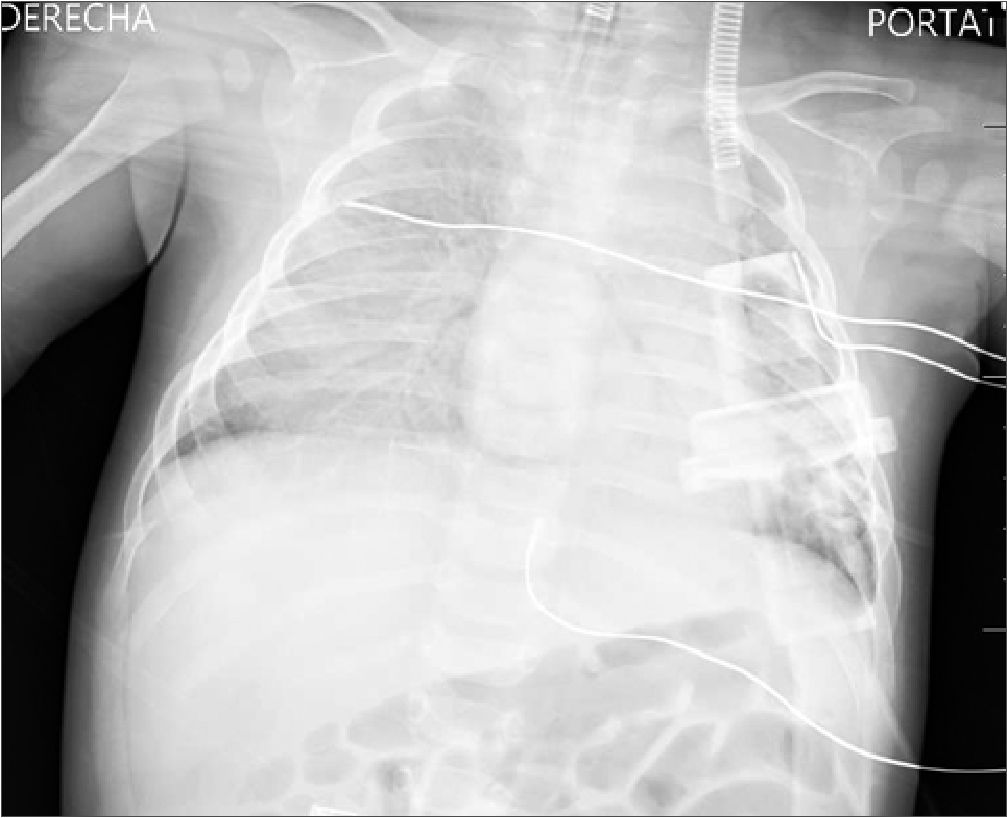

Siendo la situación estable, una vez comenzada la introducción del endoscopio y el suero de irrigación, a los 20 min se produce un episodio de hipertensión sistémica brusca (TA de 150/100), acompañada de bradicardia (FC de 100 lpm), desaturación (SpO2 en descenso desde 100 hasta 70), hipocapnia (ETCO2 de 24) y aumento de presión pico (35) en vía aérea. A la auscultación pulmonar aparecen crepitantes bilaterales y por la aspiración del tubo endobronquial se objetiva salida de líquido claro mezclado con moco. Se comunica al equipo neuroquirúrgico la necesidad de parar la cirugía para resolver la situación. Ante la sospecha de un edema agudo de pulmón, se suspende la infusión de líquidos y hemoderivados y se administra furosemida hasta un total de 6,5 mg/kg intravenoso. Para tratar de mejorar la ventilación, por posible broncoespasmo asociado, se administra salbutamol por cámara 6 puff, sulfato de magnesio 25 mg/kg, ketamina 2 mg/kg e hidrocortisona 1 mg/kg intravenoso acompañada de ventilación manual con FiO2 100%. Se producen recuperaciones parciales de SpO2 hasta 90-95%, pero con intervalos de caída de nuevo hasta 68%-70%. Se realiza placa de tórax intraquirúrgica (Figura 1) que aparenta de aumento de densidad del pulmón derecho con broncograma aéreo y pequeña cantidad de líquido en cisura menor. No se objetivan claros signos de cardiomegalia, aunque la proyección se encuentra ligeramente rotada y el borde cardíaco derecho no se define adecuadamente.

Figura 1. Radiografía anteroposterior de tórax que a pesar de la exploración subóptima técnicamente por la posición quirúrgica objetiva aumento de densidad del pulmón derecho.